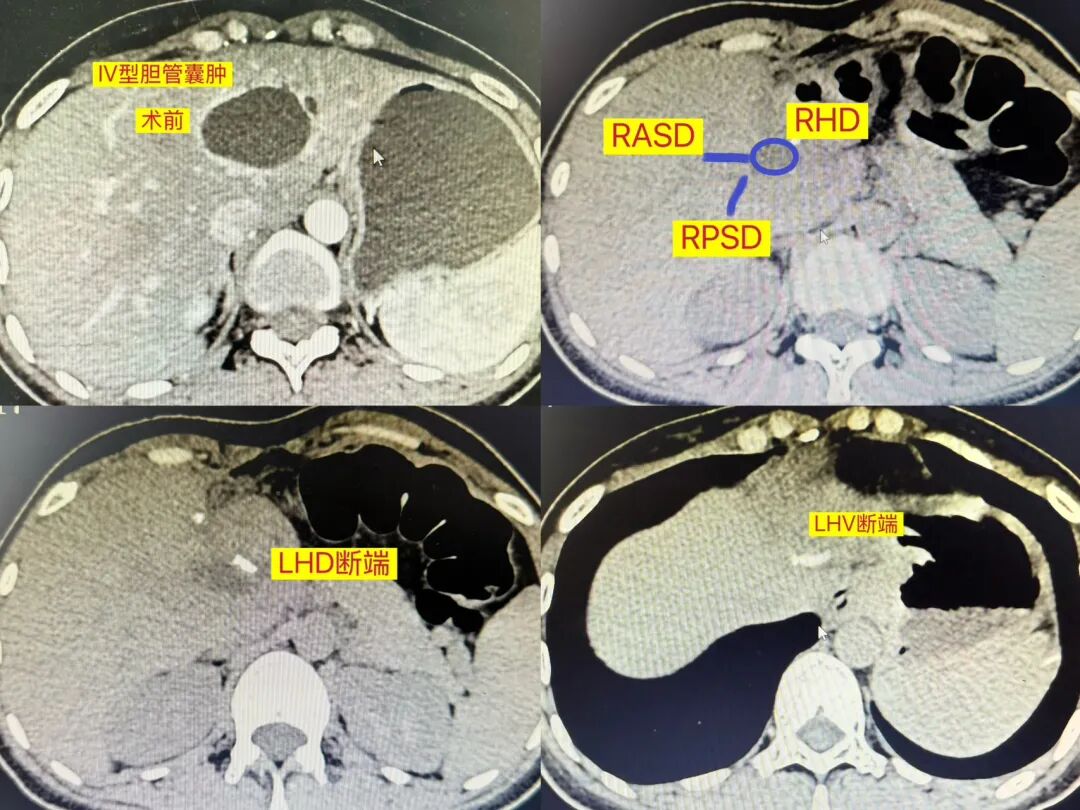

影像评估:这是一个IVA型胆总管囊肿。1.胆管:左肝内胆管囊肿与左肝管相连,右前、右后正常汇合成右肝管,右肝管稍扩张,左右肝管汇合成肝总管及胆总管,走形正常;2.肝静脉与门静脉:胆管囊肿靠近MHV,横跨LHV;3.动脉:HA分出RHA和LHA,无MHA,RHA从CBD背侧入肝。

手术规划:IVA型涉及肝内囊肿,如肝内病变局限,可行肝叶或段切除。术前评估胆道、血管系统未发现明显解剖变异,我的思路是在肝外、鞘内解剖离断LHA和LPV,取得缺血线后循MHV的体表投影,前入路沿缺血线从头侧往足侧、腹侧往背侧、由浅入深劈肝,以切缝在左肝管膨大之前离断左肝蒂,顺MHV走行往上解剖出LHV并离断。虽然右肝管汇入肝总管前有轻度扩张,但若追求此处切除,则需进行左三肝切除,同时右前、右后胆管需分别进行胆肠吻合,实在无任何必要强行加戏。病人术后复查CT恢复良好,右前、右后肝管汇入右肝管正常,随访至今无异常。